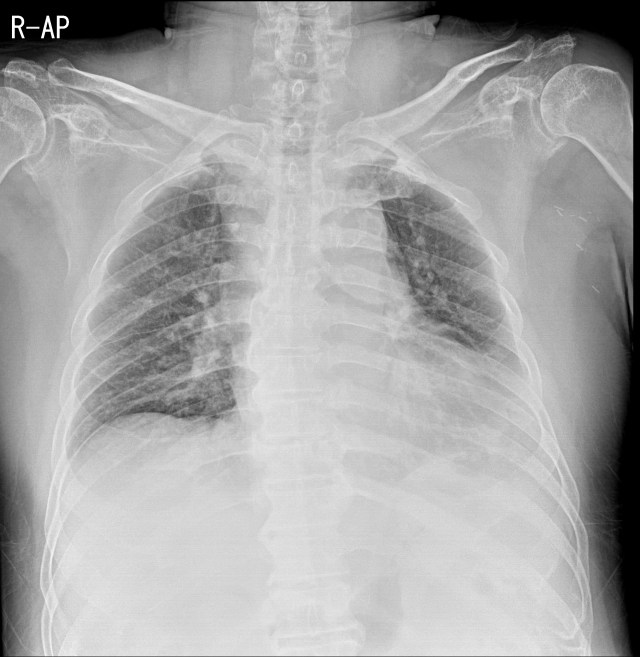

환자는 발열과 함께 증상이 심해져서 입원해서 누워있는 상태로 chest AP view영상을 촬영했습니다. 늑막삼출이나 다른 병변은 보이지 않고, 앞서 보였던 좌측심장경계의 소실 소견은 여전히 보이면서, 좌측 횡격막경계도 희미하게 보입니다.